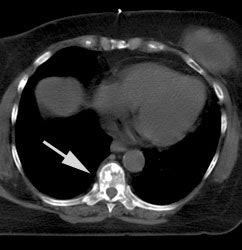

Monitoring response to therapy: The patient shown below had received chemotherapy for treatment of metastatic breast cancer (pre-therapy scan is on the left). The post-therapy scan (right image) demonstrated a very good response to treatment, however, several foci of tracer uptake remained (black arrows) consistent with residual metastatic disease. Further therapy was planned as a result of the PET scan. |